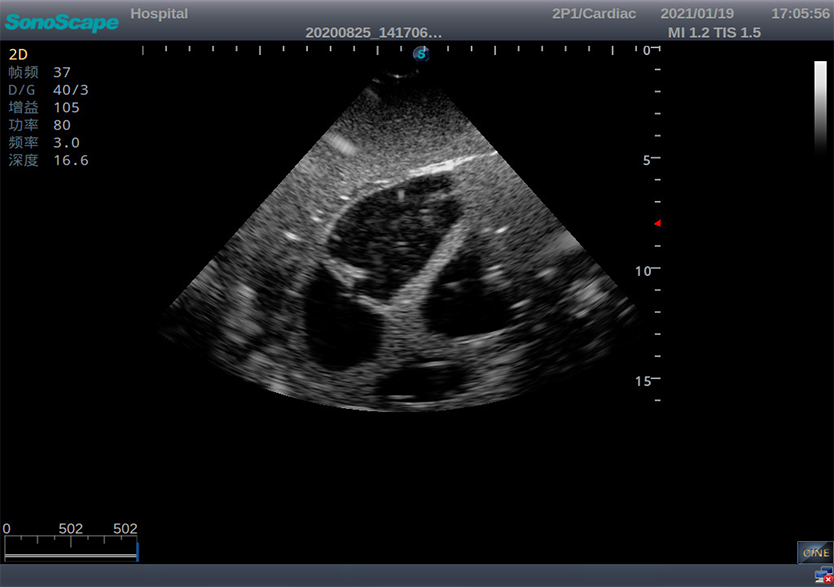

创伤超声重点评估平台2.0

产品型号 NO.TY4084

产品尺寸(mm) 987×444×269